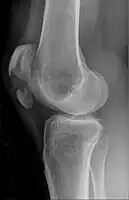

Transverse fracture of patella

Comminuted fracture of patella

Osteochondral fracture of patella- Vertical patella fracture